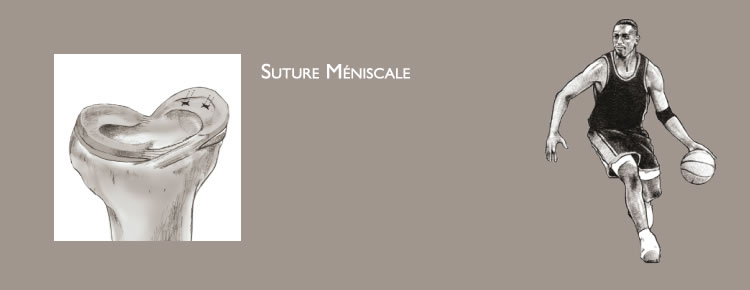

Le genou correspond à l’articulation entre la partie basse du fémur et la partie haute du tibia. Les surfaces articulaires sont recouvertes de cartilage. Les ménisques sont de petits coussins en forme de croissant qui améliorent le contact et jouent le rôle d’amortisseurs entre le fémur et le tibia (figure 1).